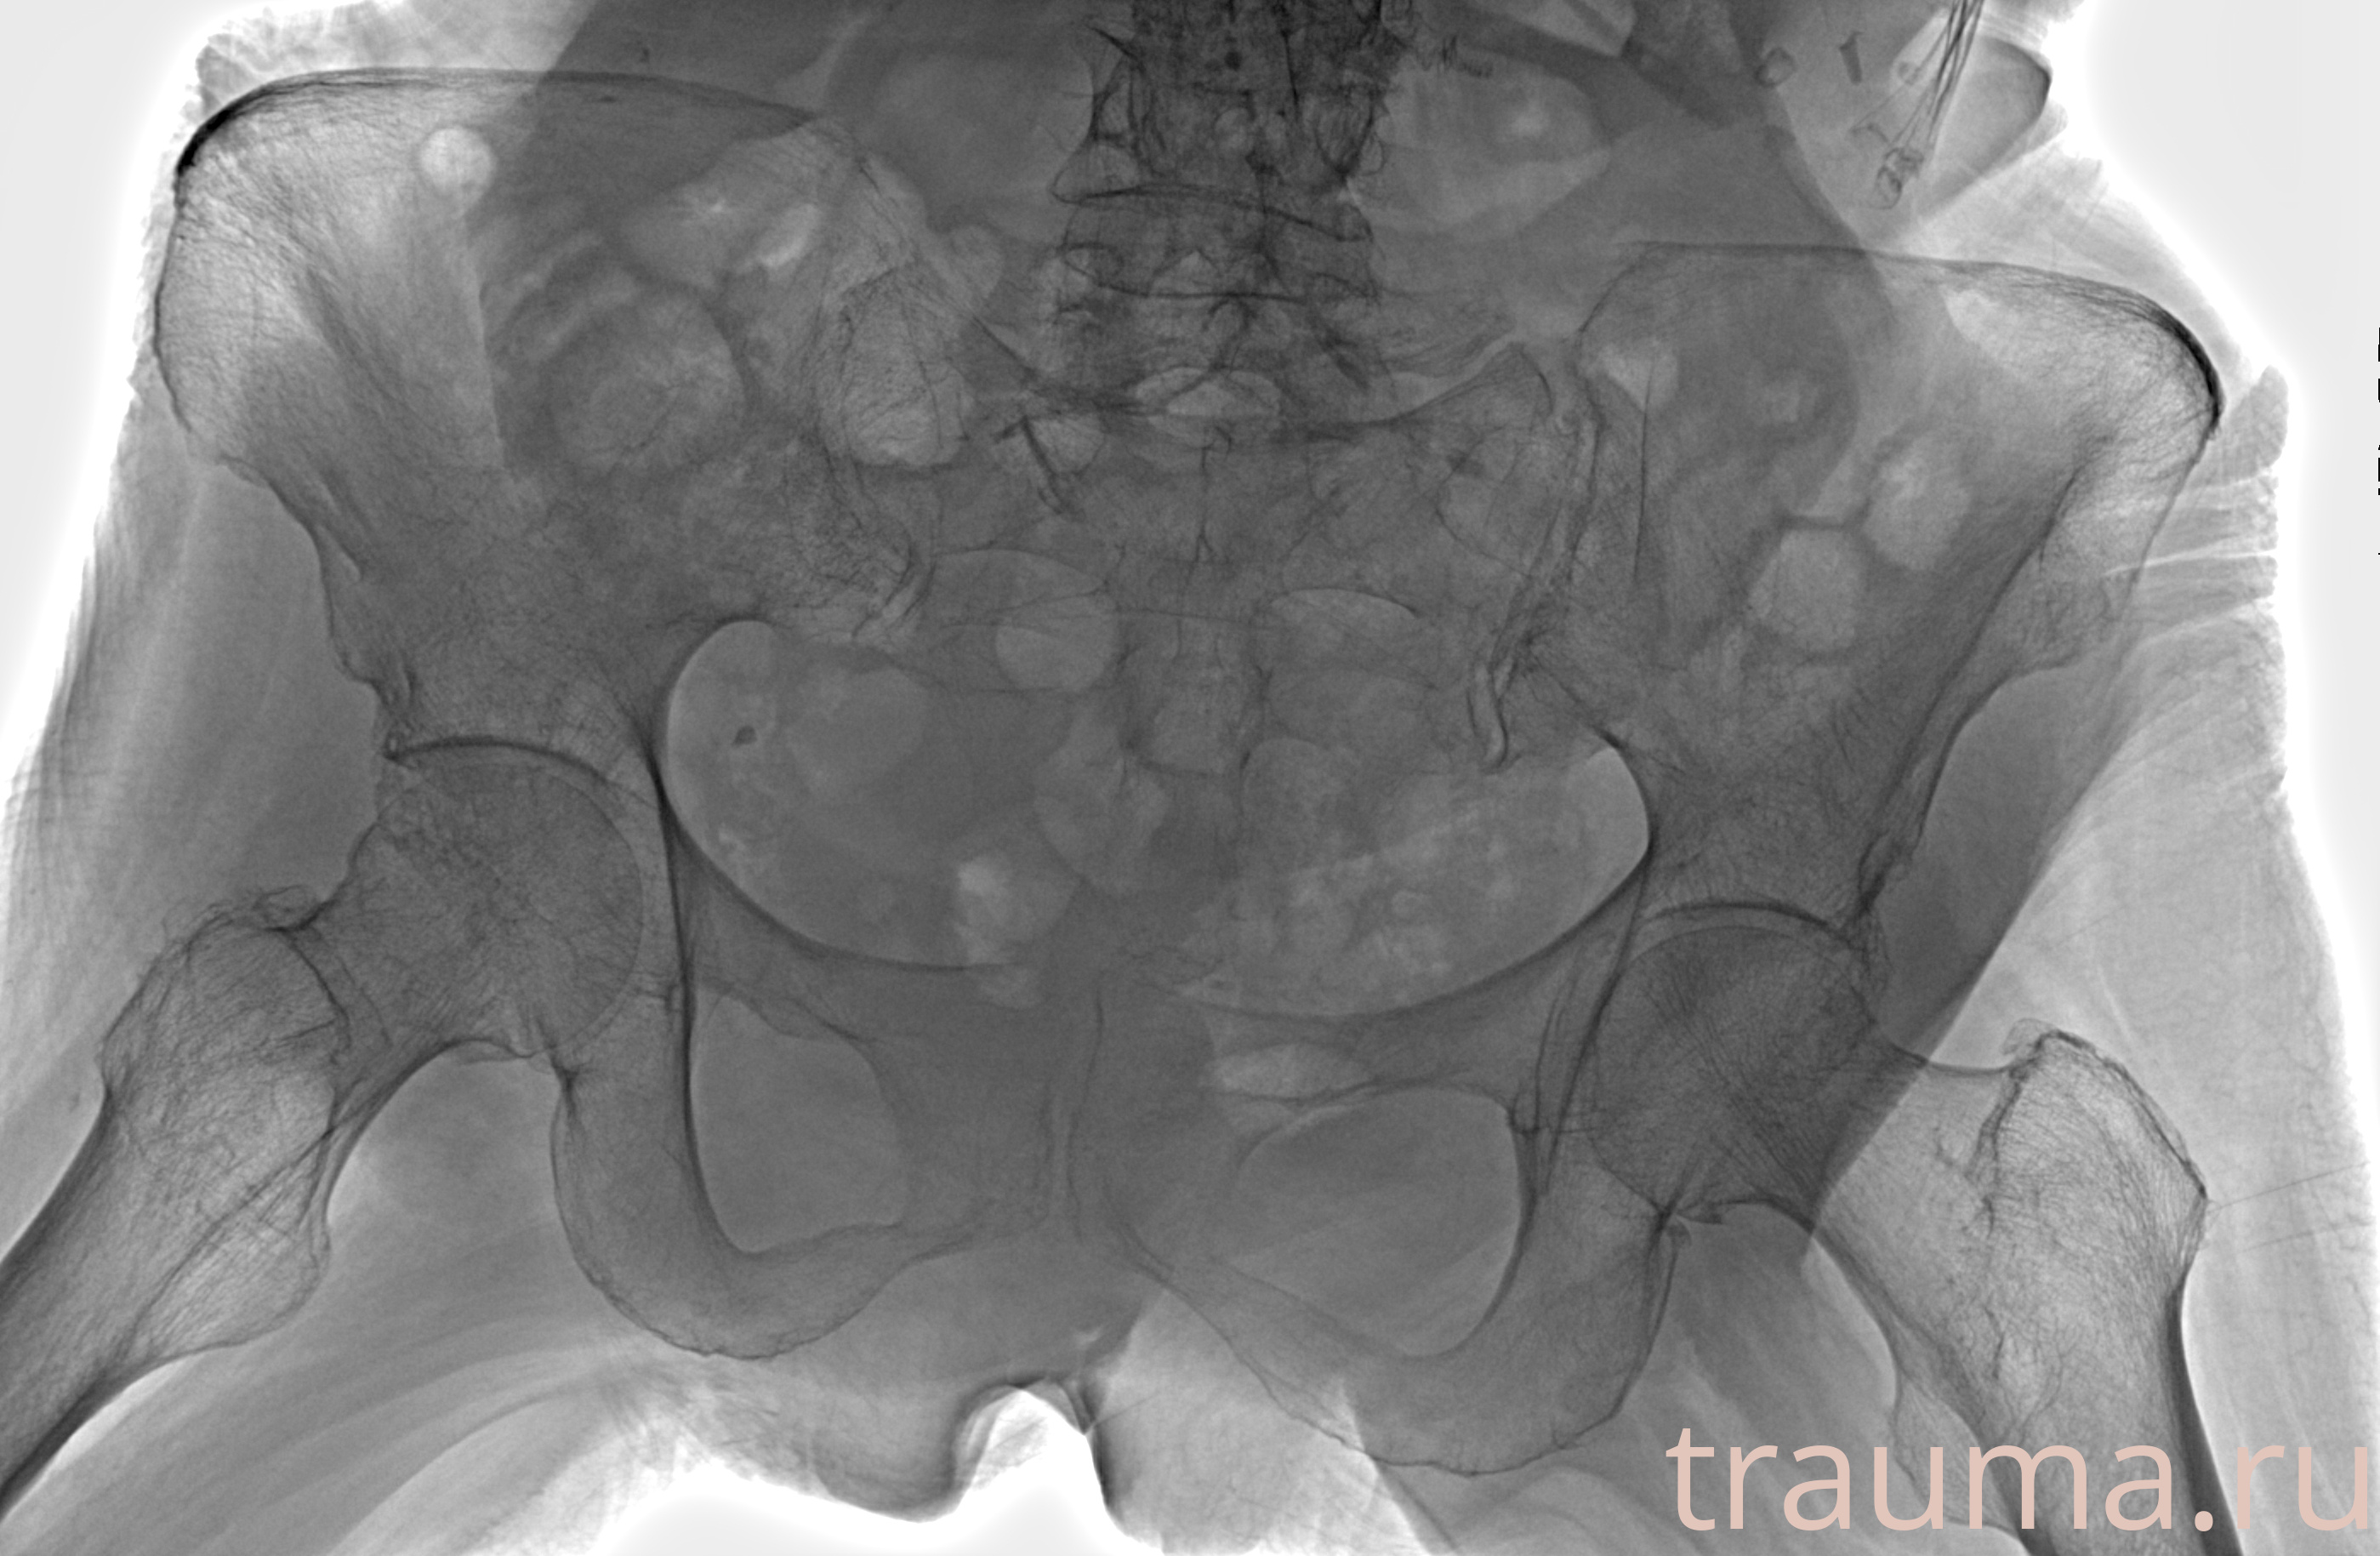

Рентгенограммы

Рентген на дому: по вашему адресу приезжает врач-рентгенолог, травматолог-ортопед с мобильным рентгеновским аппаратом, проводит диагностику травмы или заболевания, делает необходимые рентгенограммы, дает рекомендации по дальнейшему лечению. Получить качественные снимки в домашних условиях возможно благодаря уникальной методике, разработанной МосРентген Центром для института  Склифосовского